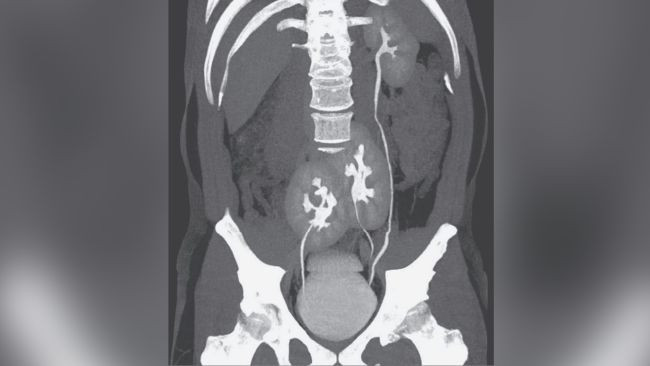

Mjekët kryen një numër testesh në përpjekje për të gjetur burimin e shqetësimit të tij, duke përfshirë një skanim CT. Rezultatet zbuluan se burri kishte tre veshka.  Një veshkë të majtë, e cila dukej normale, gjithashtu edhe dy që ishin shkrirë së bashku të pozicionuar në legenin e tij.